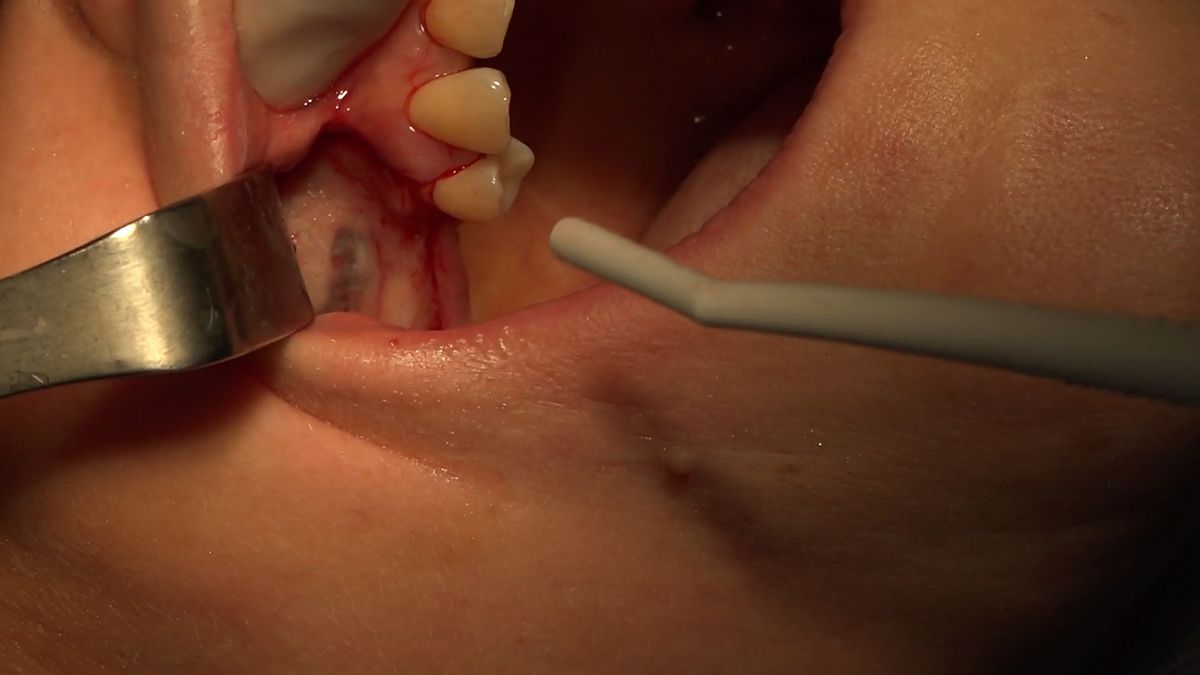

Practiculum Implantologii – Sezon VIIB, sesja 7, dzień 2